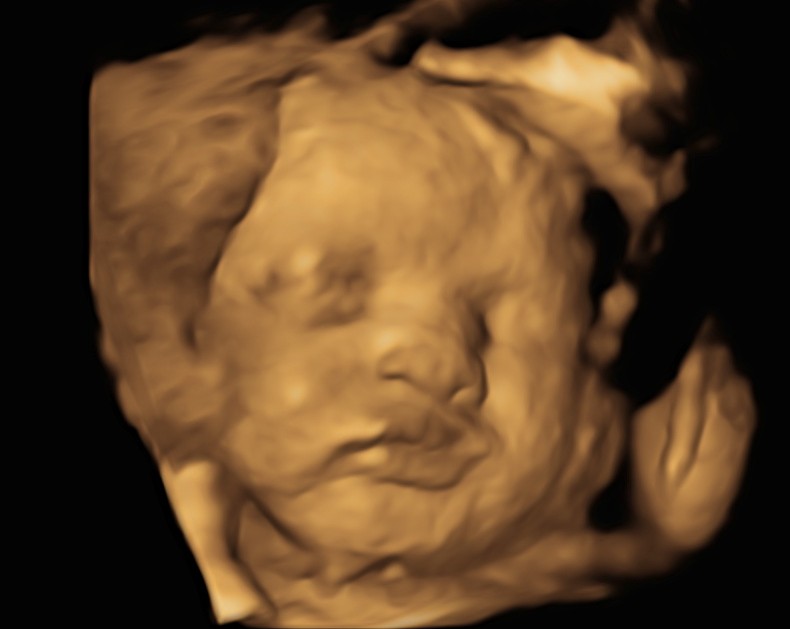

3D/4D Scan

Please tell the sonographer if you would like a sneak peek at the baby in 3D/4D.